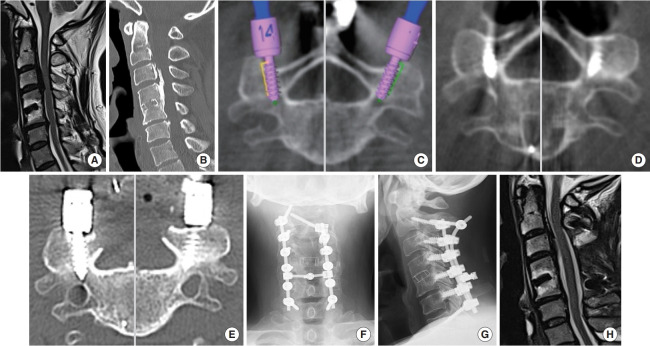

目的:与椎弓根螺钉相比,椎旁孔螺钉(PVFSs)具有更好的拉拔强度和更低的椎动脉和神经损伤风险。虽然最初的方法涉及使用侧位透视插入,但其可靠性可能有限。该报告首次评估了导航下PVFS插入的准确性。鉴于与导航系统相关的固有不准确性,作者提出并评估了一种新的逐步插入PVFS的方法,称为逐步PVFS,重点是实现正确的螺钉尖端位置,以获得良好的皮质骨购买。方法:作者回顾性分析了2022年10月至2024年2月期间在o型臂导航下采用PVFS逐步固定颈椎的12例患者(78枚螺钉)。术后计算机断层扫描(CT)评估螺钉放置的准确性。结果:共植入pvfs 78枚,男性5例,女性7例,平均年龄75岁(52 ~ 85岁)。平均随访时间为471天(47 ~ 834天)。没有与螺钉置入相关的不良事件。术后CT扫描显示70颗螺钉(90%)放置在理想位置。未达到理想位置的8颗螺钉中,4颗发生外侧偏移(位于外侧肿块),4颗过短。最后随访无螺钉松动病例。结论:本研究表明,与以往的研究报道相比,导航引导下的逐步PVFS方法在PVFS放置方面具有更高的准确性。

Methods: The authors conducted a retrospective analysis of 12 patients (78 screws) who underwent cervical spine fixation with stepwise PVFS under O-arm navigation between October 2022 and February 2024. The accuracy of screw placement was evaluated using postoperative computed tomography (CT) scans.

Results: A total of 78 PVFSs were inserted in 5 men and 7 women, with an average age of 75 years (range, 52-85 years). The mean follow-up period was 471 days (range, 47-834 days). There were no adverse events related to screw insertion. Postoperative CT scans revealed that 70 screws (90%) were placed in the ideal position. Among the 8 screws that did not achieve the ideal position, 4 had lateral deviation (located in a lateral mass), whereas the other 4 were too short. There were no cases of screw loosening at the final follow-up.

Conclusion: The present study demonstrates that the stepwise PVFS method under navigation guidance achieves higher accuracy in PVFS placement compared with conventional fluoroscopy-guided PVFS, as reported in previous studies.